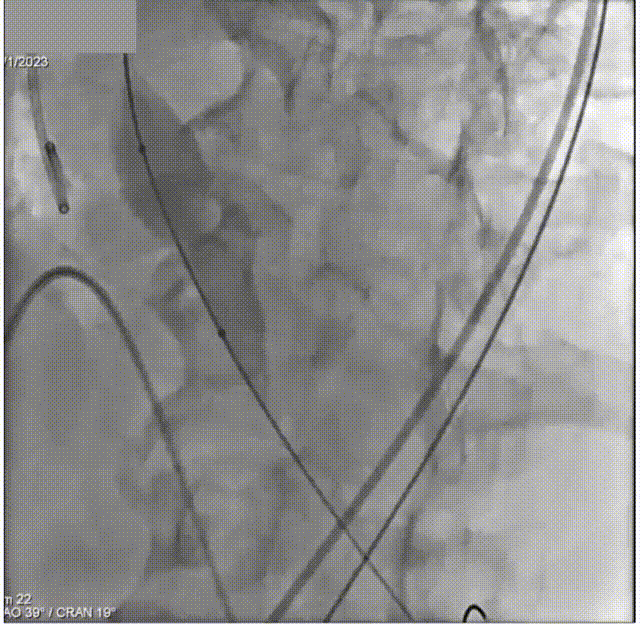

于右室放置起搏导线。穿刺外周动脉,行主动脉根部造影

导丝跨瓣

交换猪尾

加硬导丝塑形